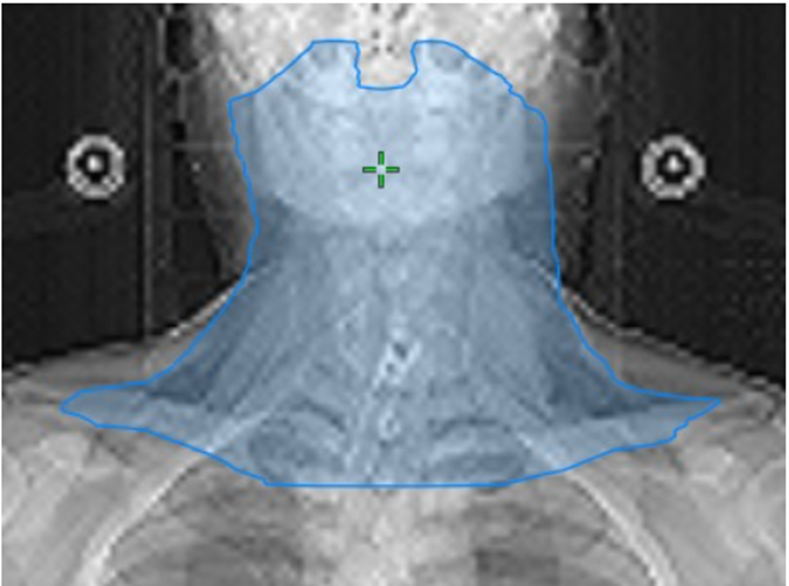

FIGURE 1

Target volume Delineation for Node positive Glottic Ca

Target volume Delineation for T1 Glottic Ca